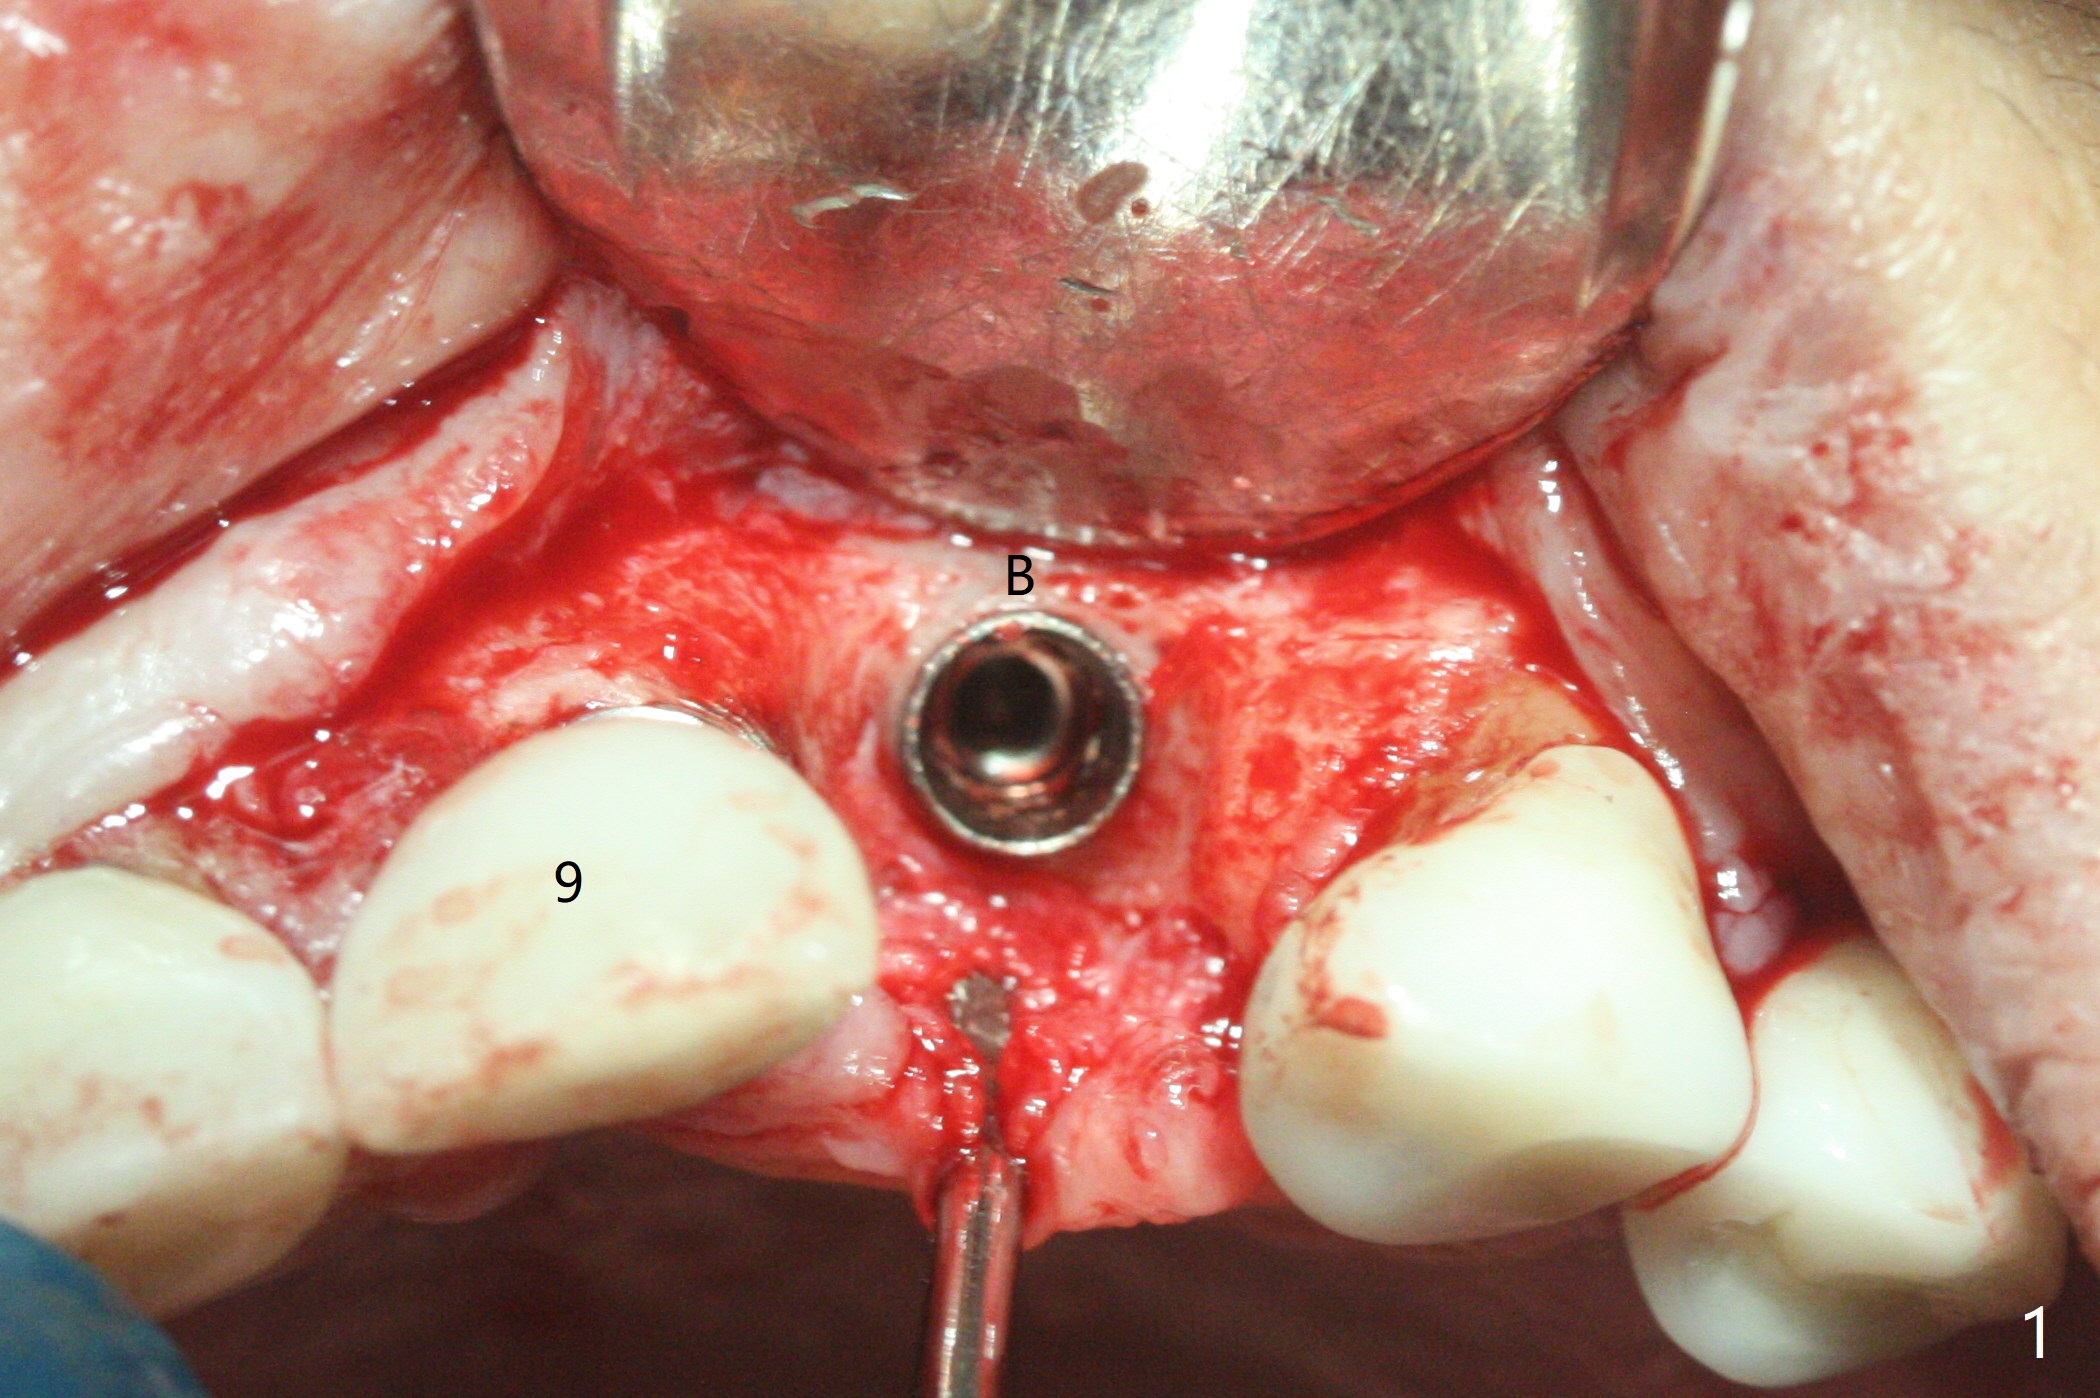

10号牙第三次种植后四年,病人主诉疼痛,颊侧牙龈缘轻度红肿,牙冠与基台取出(没有使用扳手,说明基台未完全就位),切开时,10号牙植体暴露却不多(图一),而9号牙植体远中微型螺纹却暴露很多(图二:*),整个植体种的不够深(图三),如果粘性骨块(*)不能解决周围炎问题,考虑拔除9号牙植体,做悬臂桥。Periodontal dressing dislodges 6 days postop (Fig.4).